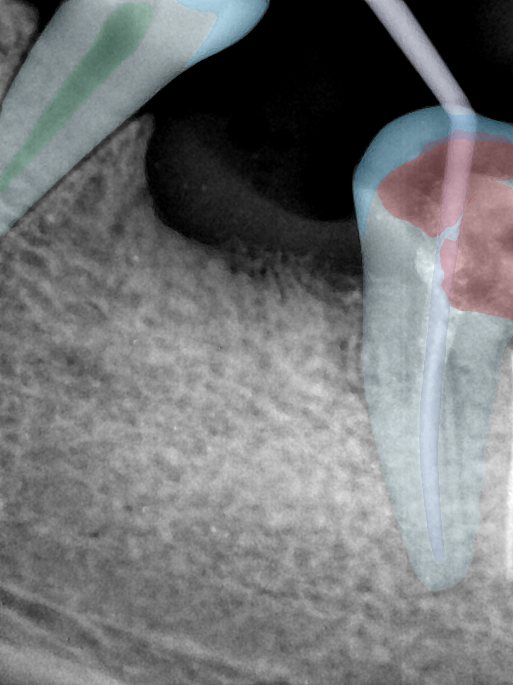

第二版算法问题测试

| 第一版 | 第二版 | 是否解决 | |

|---|---|---|---|

![]() | ![]() ![]() 边角识别有问题 龋齿识别不全 牙髓识别不全 | ![]() | 解决 |

![]() | ![]() 边角识别有问题 识别信息有误 自查(牙冠识别不全) | ![]() | 解决 |

![]() | ![]() ![]() 边角识别有误 大范围填充识别遗漏 | ![]() | 解决 |

![]() | ![]() 识别信息不全 | ![]() | 解决 |

![]() | ![]() ![]() 边角问题 牙胶识别不全 牙冠识别不全 | ![]() | 解决 |

![]() 换图片 | ![]() | ![]() 牙冠部分稍微白了一些就识别成小范围修补,部分判断异常 | 部分解决,修复类略敏感,牙冠部分稍微白了一些就识别成小范围修补,部分判断异常。 |

![]() | ![]() ![]() 牙冠识别不全 牙髓不全 根尖炎龋齿识别有误 | ![]() | 解决 |

![]() | ![]() | ![]() | 解决 |

![]() 换图片 | ![]() | ![]() | 解决 |

![]() | ![]() 牙冠识别有误 | ![]() | 解决 |

![]() 换图片 | ![]() ![]() 边角识别有误 | ![]() 修复类敏感 | 部分解决,图像过白,导致修复类判断异常。 |

![]() 换图片 | ![]() 牙冠识别不全 | ![]() 修复类敏感 | 部分解决,图像过白,导致修复类判断异常 |

结论:修复类出现了不鲁棒的情况,后续需要加入轮廓的扩充数据进行增强。